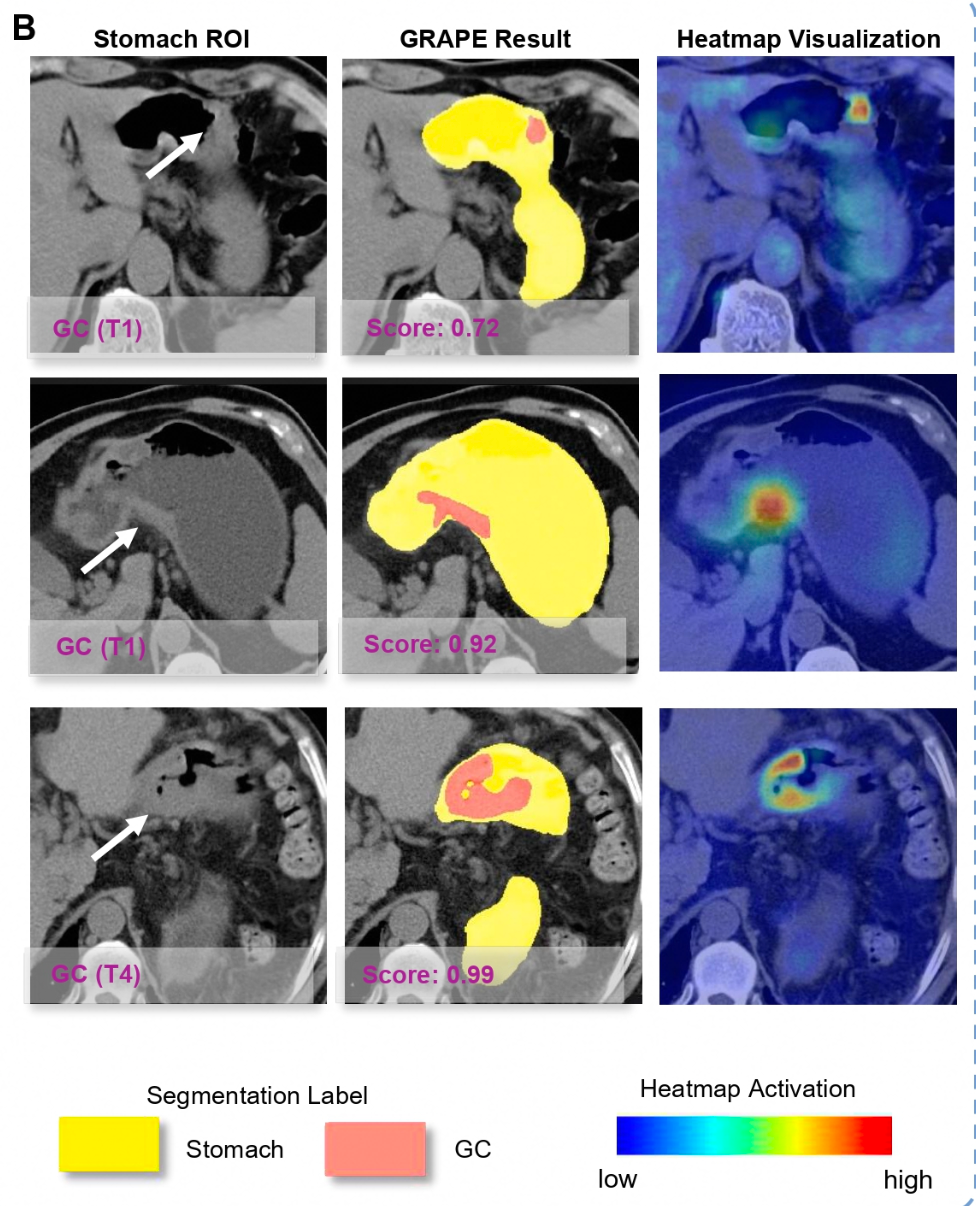

论文通讯作者、达摩院资深算法专家张灵介绍,平扫CT是体检和门诊常用的非侵入式检查,成本低、效率高,但通常认为不适宜检查胃肠道等空腔脏器。此次,联合团队突破行业固有认知,构建了国际上规模最大的胃癌平扫CT影像多中心数据集,并克服了胃部形态变化大、内部内容物干扰、早期病灶限于黏膜层等挑战。DAMO GRAPE的敏感性和特异性分别达到85.1%和96.8%,相比起放射科诊断医生分别提升21.8%和14.0%。这令平扫CT识别早期胃癌首次成为可能,也让“平扫CT+AI”在多癌筛查上更进一步。

AI成功从平扫CT种识别早期胃癌